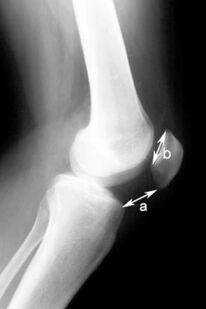

Индекс Катона является соотношением расстояния от нижнего края надколенника до передне-верхнего угла большеберцовой кости к длине суставной поверхности надколенника (рис. 3). В норме это соотношение обычно равно 1± 0,3.

Рисунок 3. Индекс Катона. Объяснения в тексте.

Индекс Катона является соотношением расстояния от нижнего края надколенника до передневерхнего угла большеберцовой кости (а) к длине суставной поверхности надколенника (b). В норме это соотношение обычно равно 1,0±0,3.

Слишком высокое расположение надколенника (patella alta) приводит к запоздалому его внедрению в трохлеарное устье, что может являться причиной надколенниково-бедренной нестабильности. Для диагностики такой нестабильности используется надколенниковый индекс.